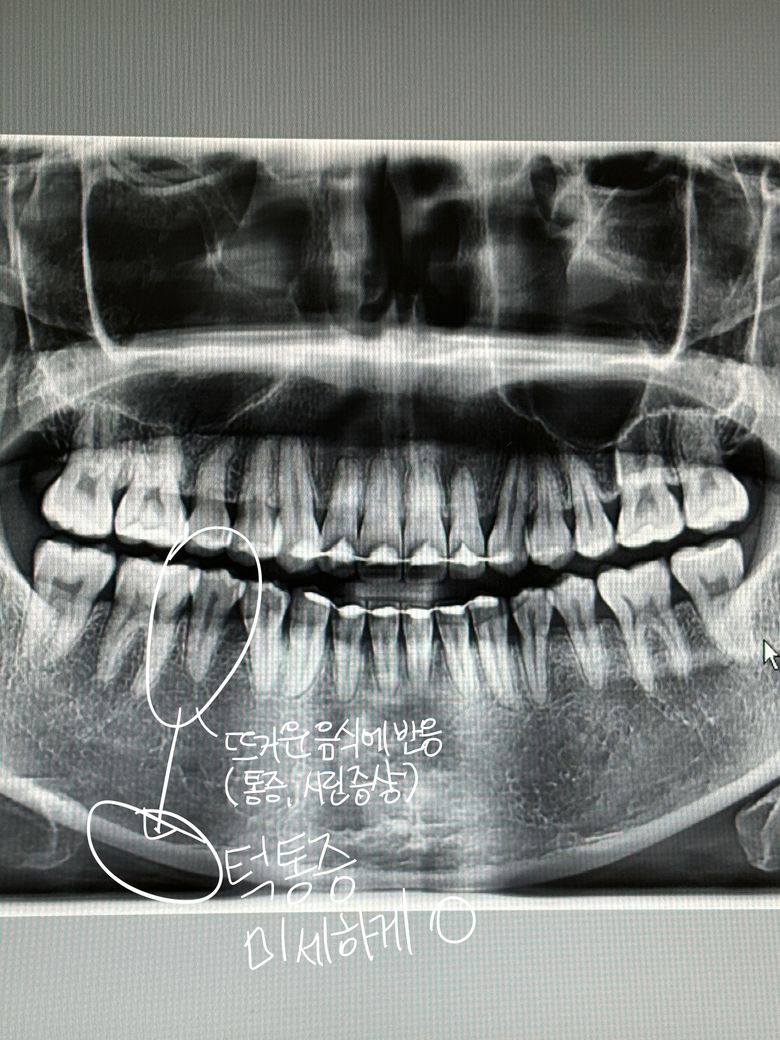

충치가 없다는데 뜨거운음식이 닿으면 이가 너무 시려요 (엑스레이사진있어요)

6월8일에 찍은 치아 엑스레이 사진 하단에 있습니다.

Q. 왼쪽 하악 어금니 하나가

뜨거운 음식만

닿았다 하면

너무 시립니다.

차가운 음식은 닿아도 괜찮습니다.

턱은 안아팠었는데 아픈 치아의 아래턱도

묘하게 신경쓰이게 아프기 시작했어요.

엑스레이상으론 특별히 이상이 있어보이지는 않습니다만 자세히 보기 위해서는 작은 치근단방사선 사진도 찍어볼 필요가 있고 다른 여러 치과 들러서 진단을 받아보시는 것도 도움이 됩니다.

치아에 뜨거운 음식에 반응을 보인다면 치수염일 가능성이 있습니다. 계속해서 불편하시면 신경치료를 하셔야될수도 있습니다.

사진으로는 크게 문제가 있어 보이진 않습니다 치아에 과도한 힘이 가해지게 되면 치아가 민감하게 되어 온도 변화에 불편감을 느낄 수 있습니다 치아에 가해지는 힘을 줄여 보시고 교합 간섭이 있다면 간섭을 조정해 주는 것이 좋을 수 있습니다.